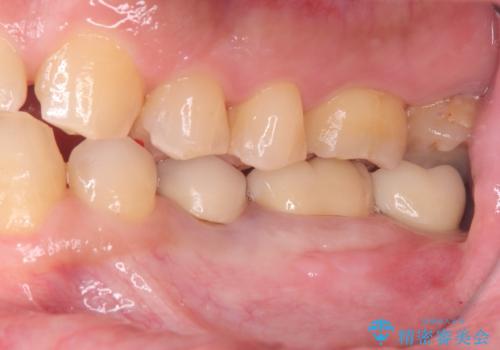

- 過去にヘミセクションが行われていたと思われる左下7番は、大きな歯根嚢胞および根尖病変が認められ、さらに骨縁下カリエスを伴っており、歯肉には瘻孔が形成されている状態でした。

保存は困難と判断し、左下7番は抜歯即時インプラントによる治療を行いました。

また、左下6番には形態が不自然で適合不良のセラミックインレーが装着されていたため、二次カリエスのリスクを考慮し、オールセラミッククラウンによる治療を行いました。